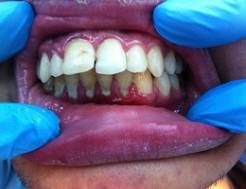

Клинический случай: пациент Е.,

20 лет, профессиональный спортсмен - единоборец, проходил курс лечения в

Стоматологической Клинике по поводу пародонтита средней степени тяжести (рис. 3 а - б.)

Рис. 3. Состояние пародонта до и после лечения

В связи с частым

возникновением аллергических реакций и других побочных эффектов при

использовании традиционных антисептиков, большой интерес вызывают природные

средства. В данном клиническом случае в комплексе с профессиональной гигиеной

осуществлялись аппликации

аппипрепаратом. Непосредственно после завершения курса альтернативной терапии

определялись нормализация цвета десны ее уплотнение, отсутствие кровоточивости.

Аналогичная положительная динамика клинического состояния околозубных

тканей выявлялась при обследовании полости рта почти у всех пациентов второй

группы.